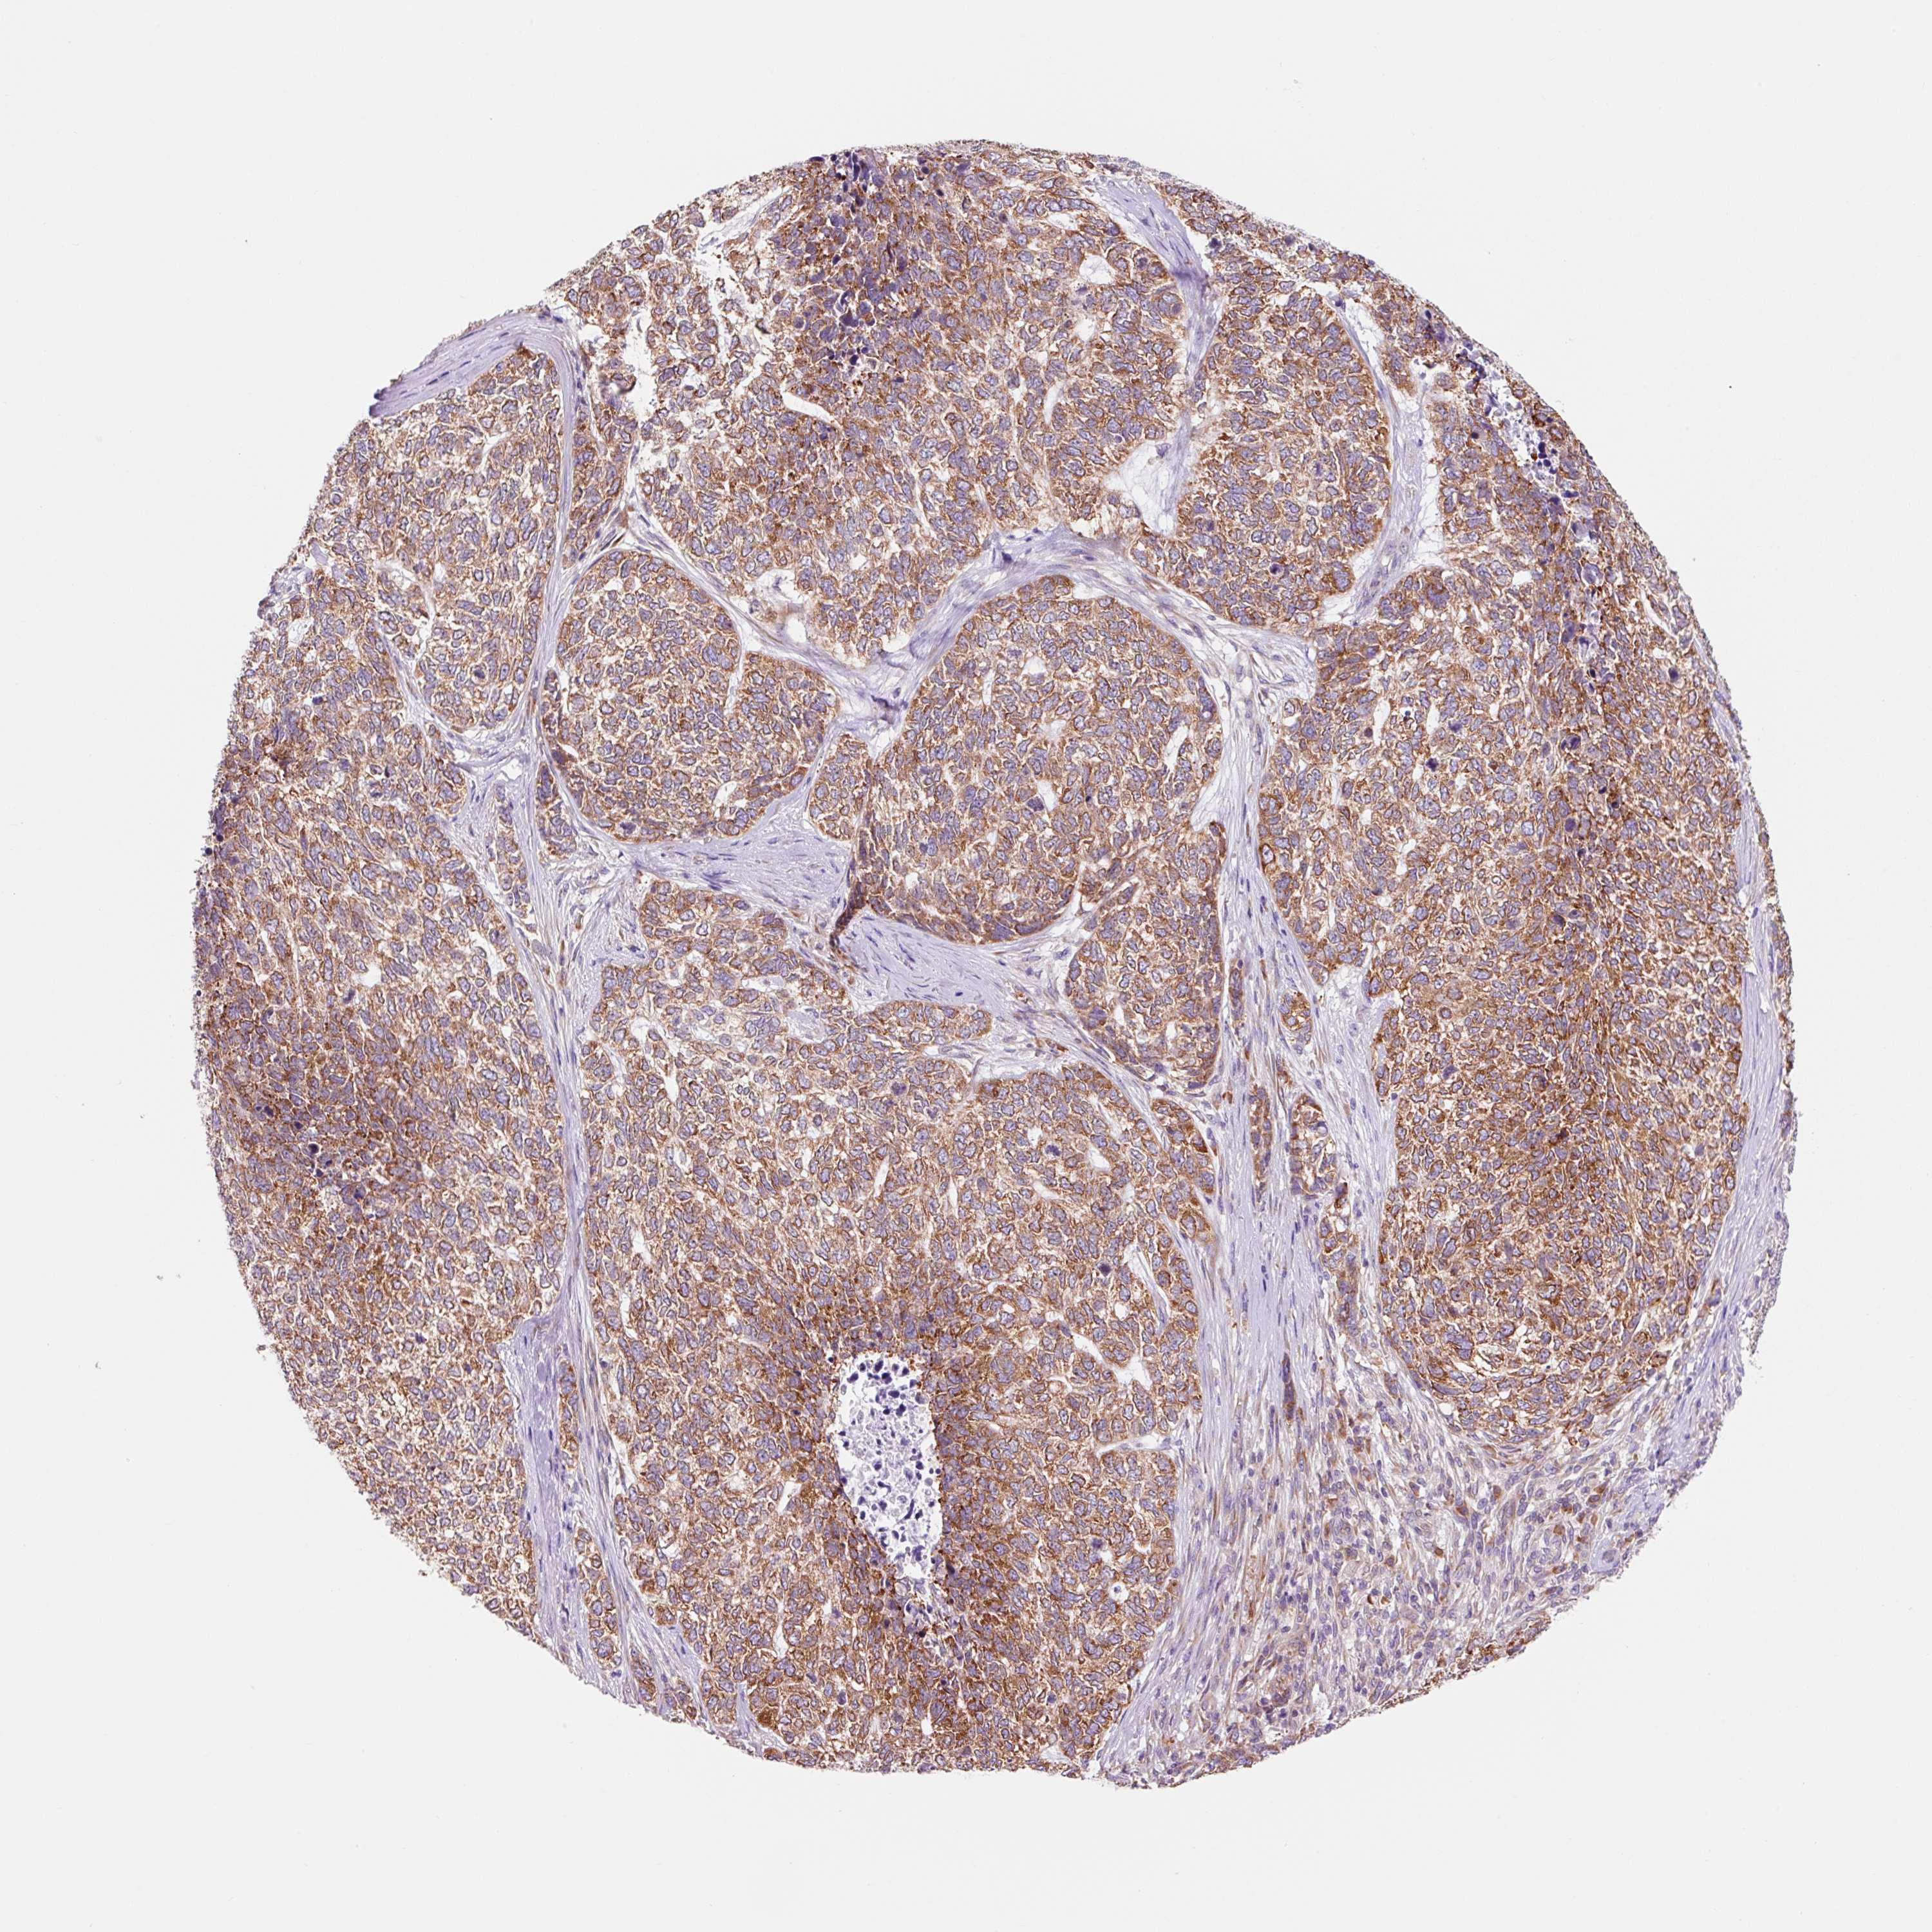

Basal cell and squamous cell cancer

SKIN CANCER - Protein expressioni

A mouse-over function shows sample information and annotation data. Click on an image to view it in a full screen mode. Samples can be filtered based on level of antibody staining by selecting one or several of the following categories: high, medium, low and not detected. The assay and annotation is described here.

Antibody stainingi

Antibody staining in the annotated cell types in the current human tissue is reported as not detected, low, medium, or high, based on conventional immunohistochemistry profiling in selected tissues. This score is based on the combination of the staining intensity and fraction of stained cells.

Each image is clickable and will lead to virtual microscopy that enables deeper exploration of all samples and also displays staining intensity scores, fraction scores and subcellular localization as well as patient and tissue information for each sample.

Antibody HPA053169

Staining

High

Strong

>75%

Location

Cytoplasmic/membranous

Basal cell carcinoma